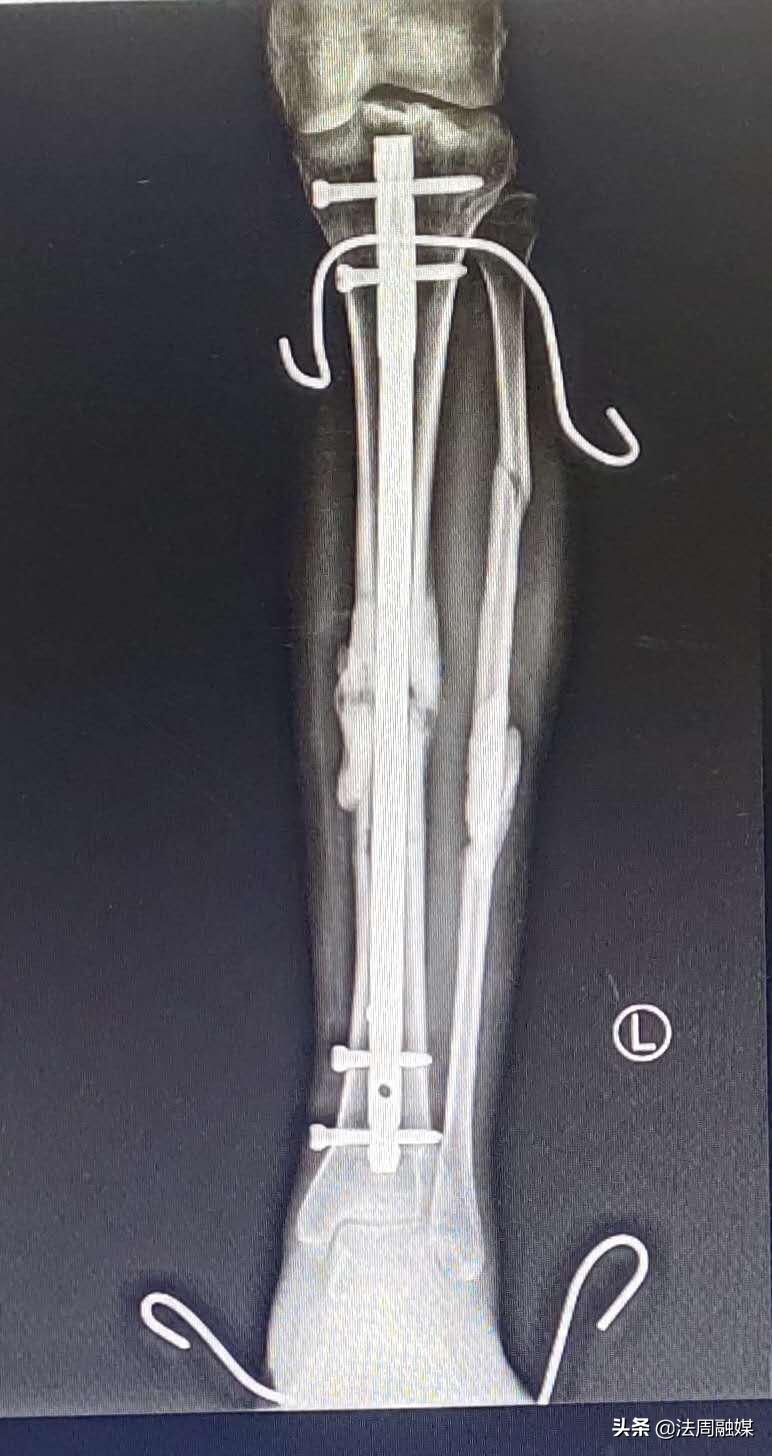

由于损伤严重,骨缺损,小文在后期康复中,骨折部位愈合不良并出现“马蹄内翻足”,站立行走困难。此时,肖群飞想出了奇招,去除外固定架,闭合扩髓达到植骨目的并髓内钉固定促进骨折愈合,再利用“克氏针配合橡皮筋”持续牵引纠正马蹄足内翻。后来,经过医生的精准治疗和自身不断的康复锻炼,小文逐渐站立起来,筑立起了明日美好的生活!

“克氏针配合橡皮筋”持续牵引纠正马蹄内翻足,可避免繁杂的畸形松解手术,使患者以最小代价得到最好的康复。